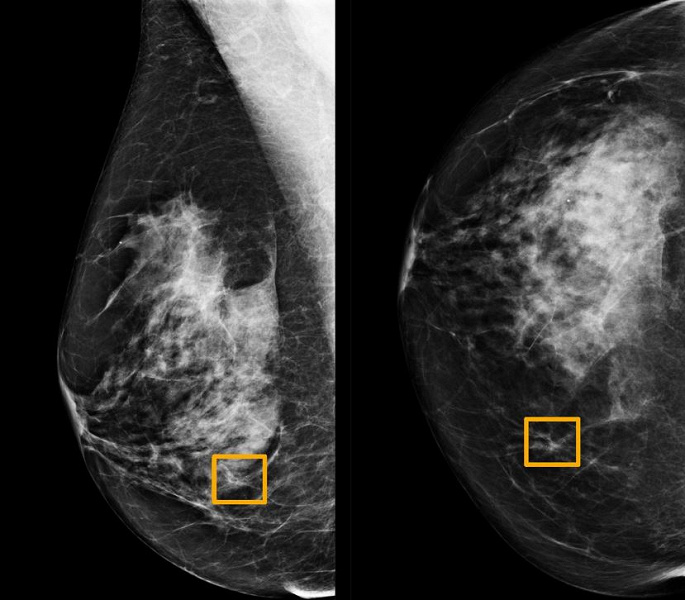

Искусственный интеллект Google выявляет рак груди точнее опытного врача

Исследование, опубликованное в журнале Nature, показало, что искусственный интеллект (ИИ) может повысить точность скрининга на рак молочной железы, которым, как утверждается, страдает каждая восьмая женщина в мире.

Изучая маммограммы, система искусственного интеллекта Google показала себя не хуже, чем опытные врачи и продемонстрировала перспективу уменьшения количества ошибок.

Система разработана компанией DeepMind, в 2014 году приобретенной холдингом Alphabet, совместно с Google Health. Команда, в которую вошли исследователи из Имперского колледжа Лондона и Британской национальной службы здравоохранения, провела обучение системы для выявления рака молочной железы на десятках тысяч маммограмм. Затем они сравнили результаты работы системы с фактическими результатами из набора 25 856 маммограмм из Великобритании и 3097 из США. Исследование показало, что система искусственного интеллекта может идентифицировать рак с такой же степенью точности, что и опытные радиологи, при этом уменьшая количество ложноположительных результатов на 5,7% в группе в США и на 1,2% в группе из Великобритании. Сократилось и количество ложных негативов, где тесты ошибочно классифицируются как нормальные — на 9,4% в группе из США и на 2,7% в группе из Великобритании.

В отдельном тесте группа сопоставила систему искусственного интеллекта с шестью радиологами и обнаружила, что она превосходит их по точности обнаружении рака молочной железы.

Дело в том, что эти системы обучены распознавать то, что и так видят радиологи, в то время как ИИ учится распознавать рак на основе фактических результатов тысяч маммограмм и в результате может выявить тонкие признаки, которые, по словам исследователей, «не замечает человеческий глаз и мозг».